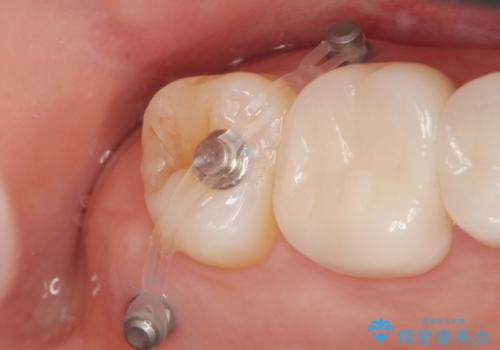

通常このような場合、神経を除去し歯を短くしたのちインプラント治療を行いますが、今回はマイクロインプラントを用いて歯を歯ぐきの方向へ沈めたのち神経を温存する形でインプラント補綴を行いました。

- 44万円(インプラント・アバットメント・ジルコニアクラウン・仮歯・小矯正)費用は治療当時の料金となります